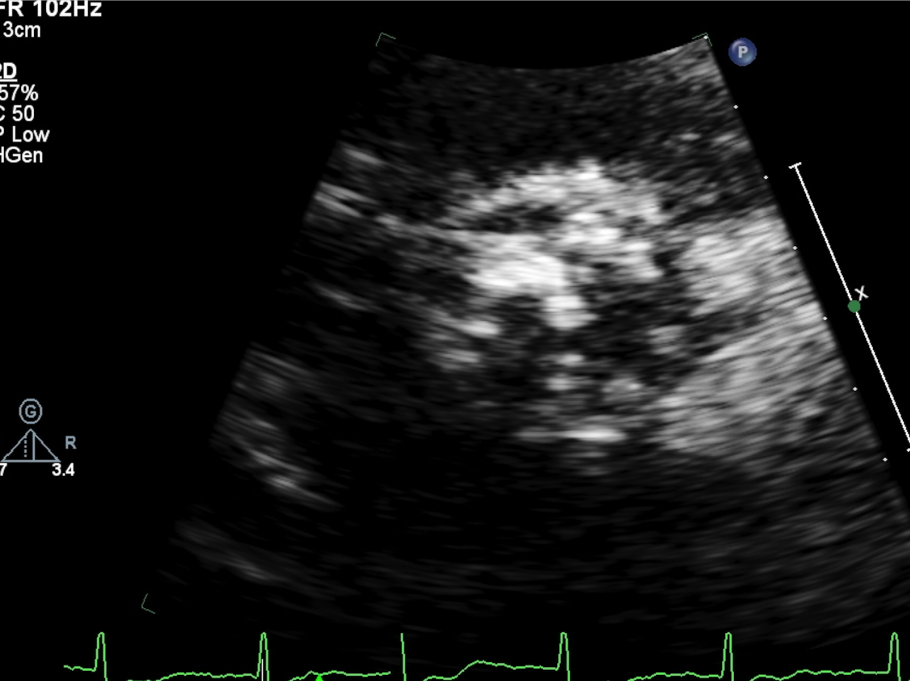

瓣膜内22mm球囊后扩张,左冠无显影

LM烟囱支架植入4.0*30mm